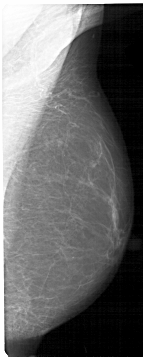

A_1178_1.LEFT_MLO

LEFT_MLO LINES 5236 PIXELS_PER_LINE 2476 BITS_PER_PIXEL 12 RESOLUTION 43.5 OVERLAY